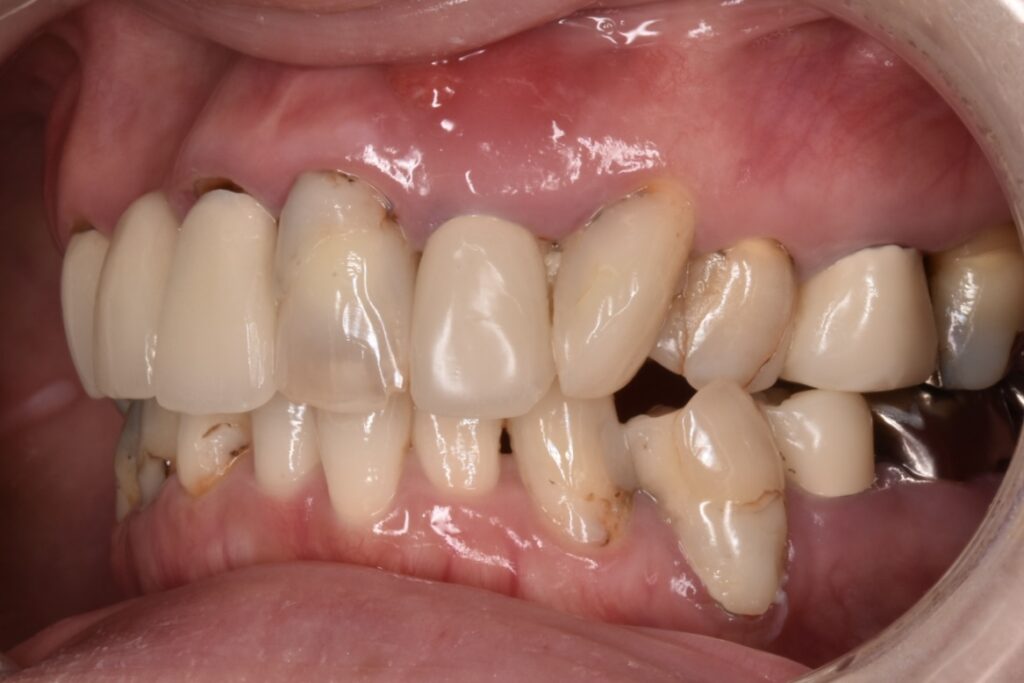

初診時の状態

各歯が自費の被せ物や保険の治療痕など歯ごとにバラバラな状態で、どれも状態が良いとは言えないものばかりでした。見た目の回復も必要ですがそれ以前に再神経処置・虫歯再治療・抜歯、噛み合わせの回復など多岐にわたる治療が必要な状態でした。

今回は上をメインに治療し下の歯は順次治療していきます。(そのようにご希望です)

上顎セラミック治療後

上の両奥歯3本ずつはさくらセラミックプラン 前歯6本匠セラミックプランで治療させて頂きました。